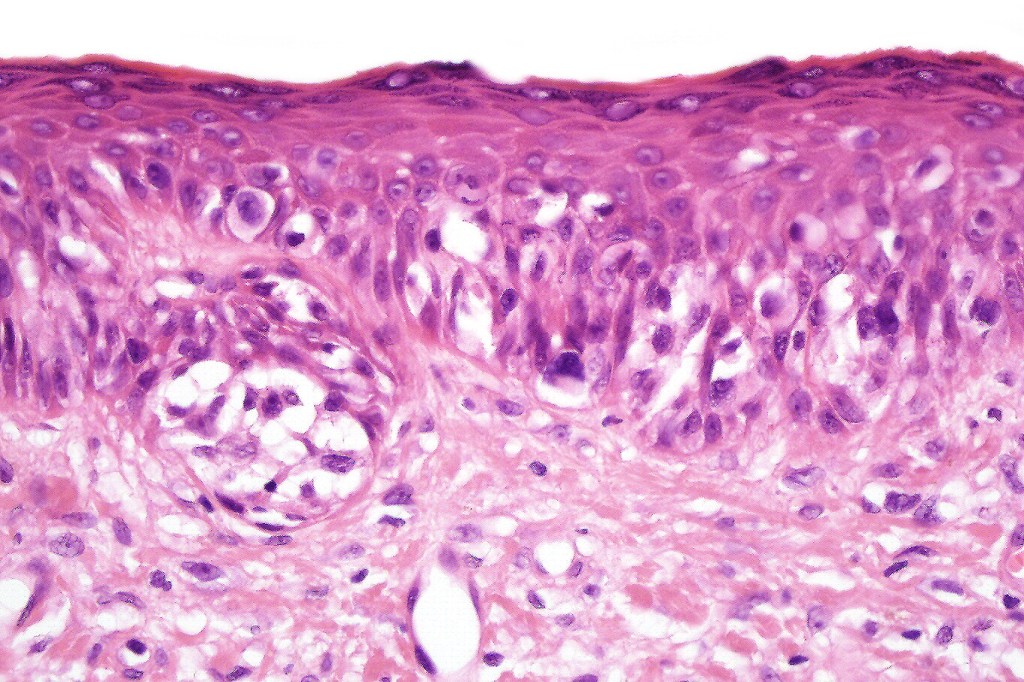

•Cytoplasmic retraction artifact, nuclear hyperchromatism with irregular borders

•Multinucleate giant cells

•Nest formation present in more advanced cases

•Pagetoid spread